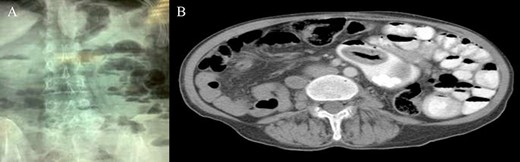

Accordingly, an exploratory laparotomy was decided upon: it revealed dense adhesions that were removed. Small bowel running brought out diffusely occurring JD (Fig. 2A), one of which, located proximally, was surprisingly giant and hard (Fig. 2B).

(A) Diffuse JD; (B) proximal large and hard jejunal diverticulum.